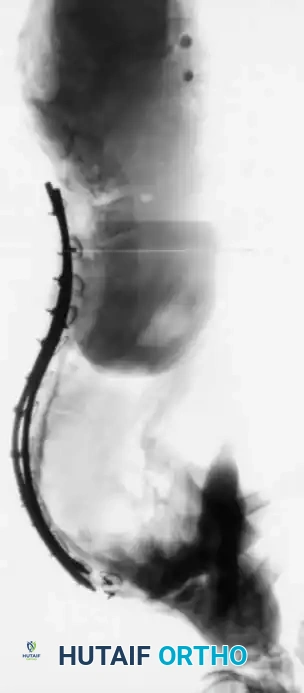

Fig. 16: Supine lateral bending radiographs demonstrating curve flexibility.

Fig. 17: Push-prone or traction radiographs may be utilized for severe, rigid curves >70 degrees to assess maximum correctability.